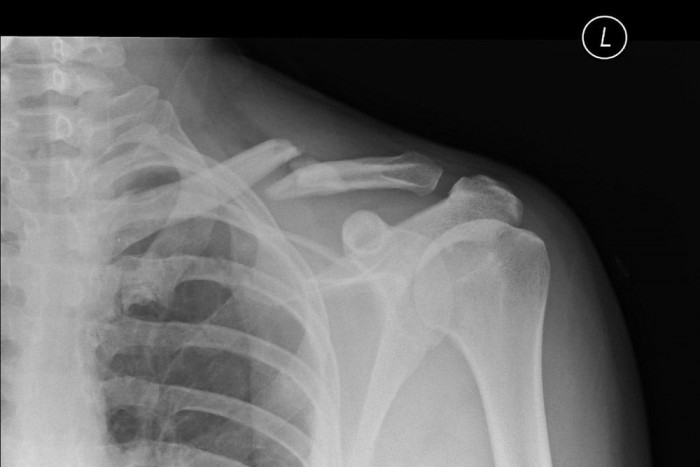

Ebben az esetben az oldallégzsák és a fejlégzsák a komolyabb törésektől is megóvhatja az embert, sőt; a szó szoros értelmében életet menthet. Nagyobb sebességű becsapódás esetén (légzsák nélkül) károsodhat a térd, a comb, számítani kell a csípővápa többszörös törésére, a felkarcsont felső részének, az ún. vállövnek törésére, az izmok és szalagok roncsolódására, valamint a nyakcsigolyák és a koponya sérülésére.